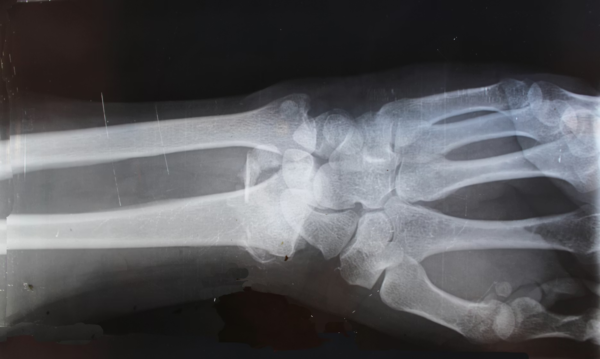

(X光照片示意图,与本文无关)